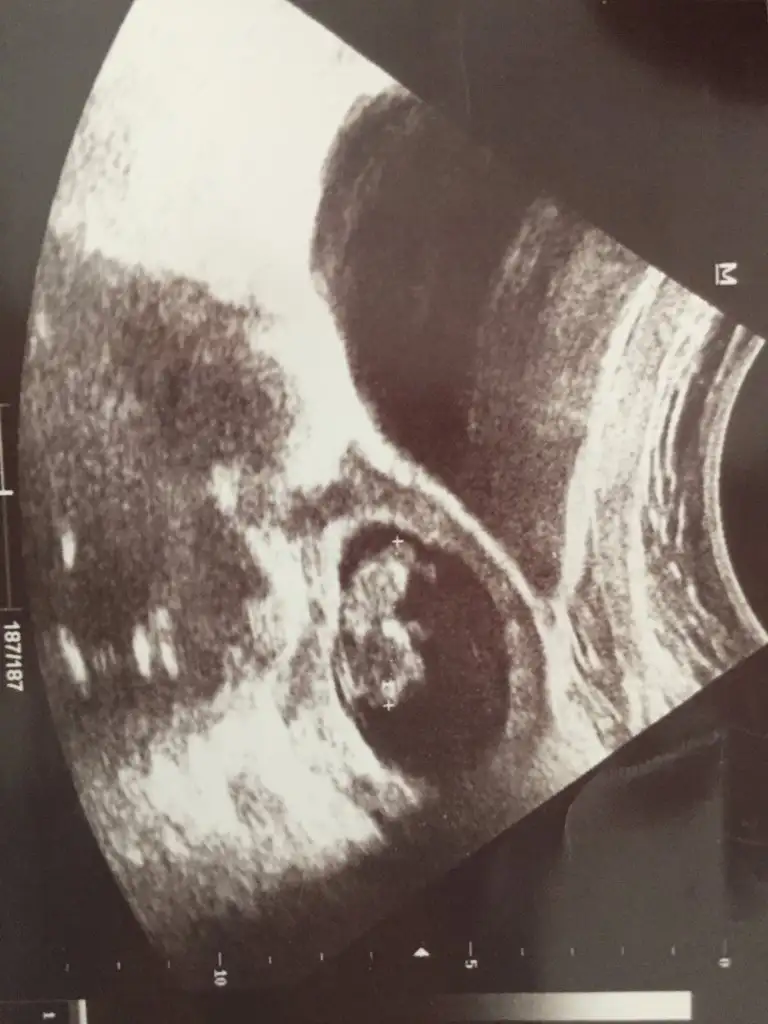

Ikra soruyorum kizma lutfen bu isaretlediklerim nubu degilmi bacagimi acabaYolk saç solda görünüyor

Hayır nub olmazIkra soruyorum kizma lutfen bu isaretlediklerim nubu degilmi bacagimi acaba

Erkek gibi başka usgde paylaşın teyit edeyim 11 12 13 haftalar olmalı USG kaç haftalıkTahmin varmi kızlar Eki Görüntüle 2671896

12+2 cnmErkek gibi başka usgde paylaşın teyit edeyim 11 12 13 haftalar olmalı USG kaç haftalık

Nub için 11 12 13 hafta olmalıMerhabaaa.. Bize de bir yorum yapabilir misiniz rica etsemEki Görüntüle 2672037 Eki Görüntüle 2672038

Nub için 11 12 13 hafta olmalı

Başka USG varmı renklide nub görünmüyor diğerinde nub çok karışık net değil